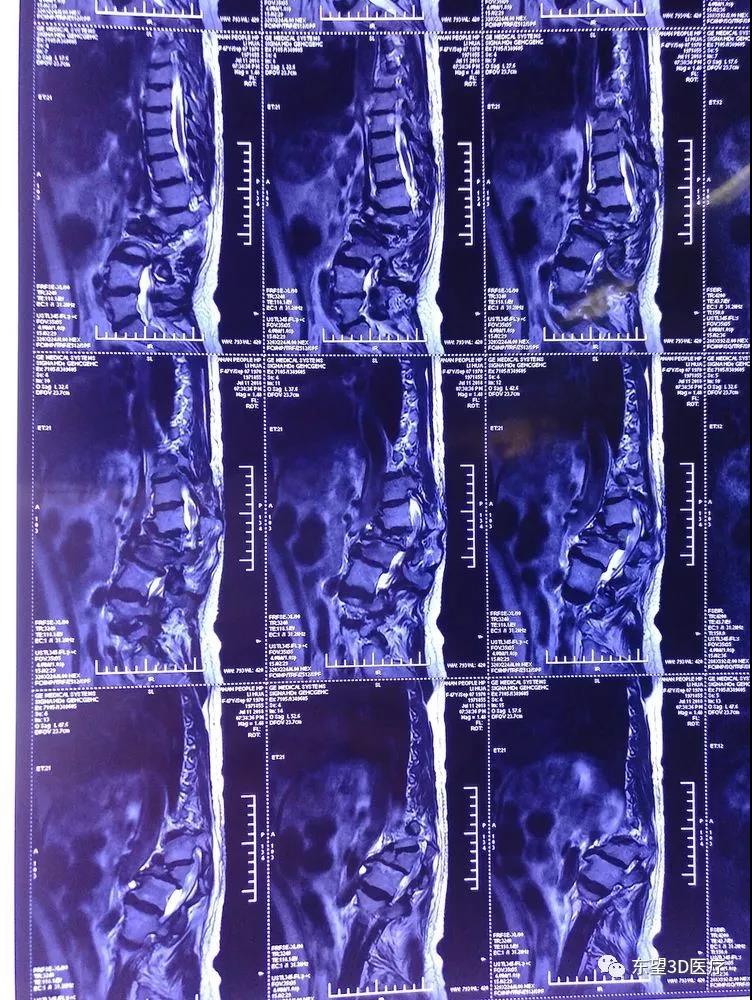

術前MRI檢查,硬膜囊脊髓明顯受壓